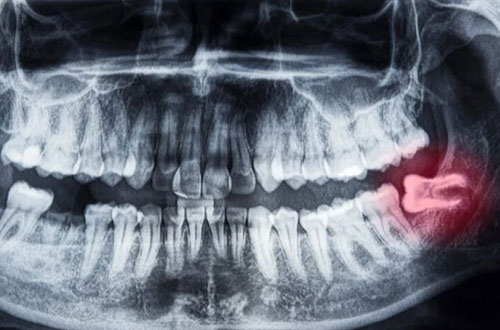

Ibland kan en operation av visdomstanden krävas och det kan då bero på att omständigheterna kring tanden gör så att den inte går att dra ut. Det kan exempelvis bero på att tanden har vuxit snett, drabbats av en omfattande infektion eller är retinerad, att tanden ligger kvar i käken täck av slemhinna och ibland även ben. Tandens rötter kan även vara böjda vilket gör att det är svårt att dra ut den. I de fall man måste ta bort en visdomstand som sitter komplicerat är operation det bästa alternativet.